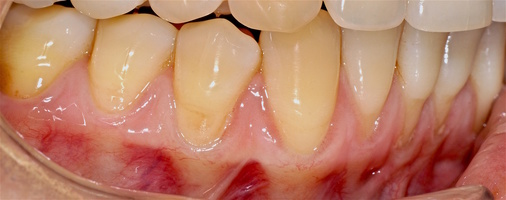

В марте 2017 года в клинику обратилась пациентка Ч., 28 лет (табл. 1) без вредных привычек, с положительным социальным статусом, астенического телосложения. С жалобами на тотальное обнажение корней зубов с повышением чувствительности от термических раздражителей, эстетические дефекты, абразии твердых тканей зубов.

Исходный объем мягкотканного комплекса атрофичен, тонкий биотип десны. Мелкое преддверие полости рта на нижней челюсти в переднем отделе, от 44-го до 34-го зубов высокое прикрепление слизисто-мышечных тяжей.

В области от 1.6 до 2.6 и от 3.6 до 4.6 все зубы имеют некариозные поражения разной степени, такие как эрозии эмали и клиновидные дефекты, вовлекающие в процесс ткани эмали и дентина. Подвижности зубов не выявлено (рис. 1а-е) [9].

При анализе и описании компьютерной конусно-лучевой томографии (рис. 2а-г) была выявлена генерализованная первичная дегисценция вестибулярной пластинки кости от 1/2 до 3/4 длины корней зубов, зубной ряд целостный, все зубы витальны, кариозных поражений нет. Тип кости 1-2 (Lechkolm и Zarb, 1983), первичная дегисценция вестибулярной костной пластинки превышает пределы возрастной атрофии.

Исходный диагноз: генерализованные рецессии десны 1 и 2 класса по Миллеру [7, 9, 10].